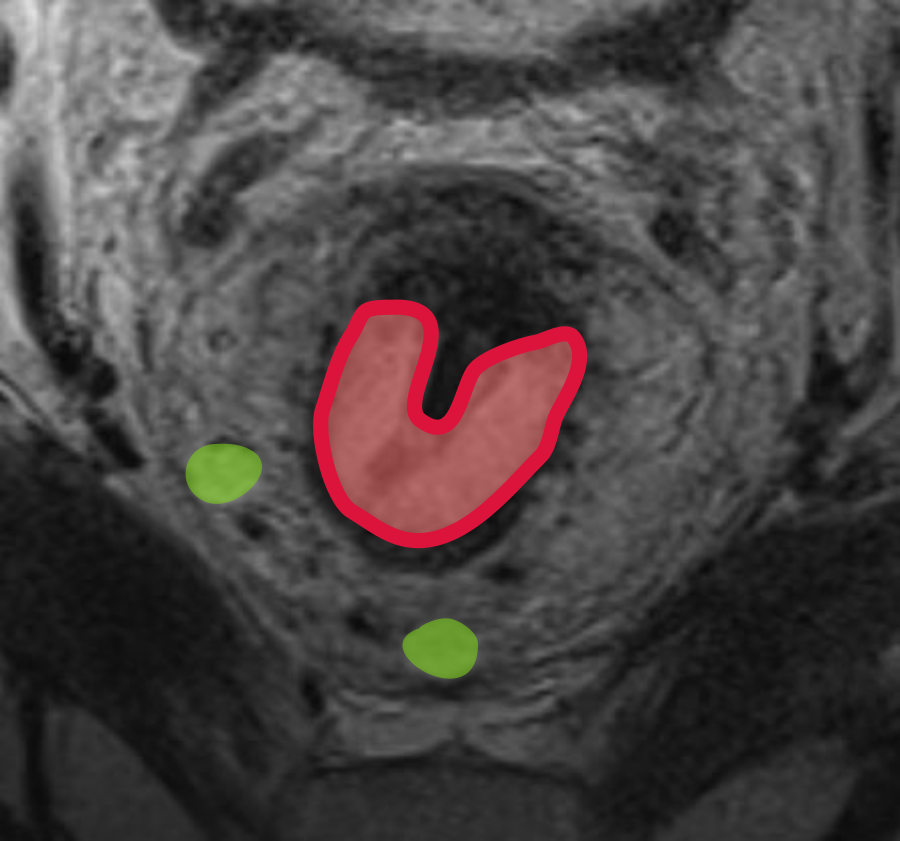

Протяженность опухоли и ее распространение по окружности описывается в условных «часах циферблата». На МРТ опухоль прямой кишки проявляется локальным утолщением стенки кишки с закругленными приподнятыми краями (рис. 2).

Высокоразрешающие Т2-ВИ срезы в корональной плоскости (по длинной оси анального канала) детально визуализируют распространенность опухолевого процесса и обеспечивают информацией, необходимой для выбора хирургического подхода.

Классификация для стадирования низкорасположенных опухолей (табл. 2) должна дополнительно применяться при описании распространенности опухолевого процесса. Данная классификация критически важна для определения показаний к межсфинктерной резекции или БПЭ, поскольку учитывает вовлечение:

сфинктера (внутреннего, наружного)

межсфинктерного пространства

- levator ani

расстояние до кожи промежности и m. puborectalis.